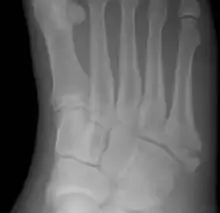

![]() | |

Jones fracture as seen on Xray | |

A Jones fracture is a broken bone in a specific part of the fifth metatarsal of the foot between the base and middle part[8] that is known for its high rate of delayed healing or nonunion.[4] It results in pain near the midportion of the foot on the outside.[2] There may also be bruising and difficulty walking.[3] Onset is generally sudden.[4]

The fracture typically occurs when the toes are pointed and the foot bends inwards.[6][2] This movement may occur when changing direction while the heel is off the ground such in dancing, tennis, or basketball.[9][10] Diagnosis is generally suspected based on symptoms and confirmed with X-rays.[3]

Diagnostic X-rays include anteroposterior, oblique, and lateral views and should be made with the foot in full flexion.